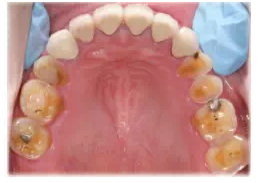

圖13將上頜模型、蠟板、石膏平臺一起上平均值牙合架,取下蠟板后,在蠟板和石膏平臺之間留下的空隙內(nèi),用白色嵌體蠟雕刻后牙的牙冠形態(tài),形成恢復(fù)上頜正常牙合平面的診斷蠟型

圖14根據(jù)診斷蠟型制作暫時冠戴入上頜。A.上頜后牙診斷蠟型;B.根據(jù)診斷蠟型翻制的暫時冠;C.暫時冠戴入口內(nèi)

圖17雙側(cè)上頜后牙采用全瓷嵌體(CAD/CAM,eMax,Vivodent Ivoclar),其他基牙采用金合金烤瓷冠修復(fù)。A上頜后牙的高嵌體基牙預(yù)備;B后牙的工作模型;C后牙全瓷高嵌體粘接中,氫氟酸酸蝕,樹脂粘接水門汀粘固